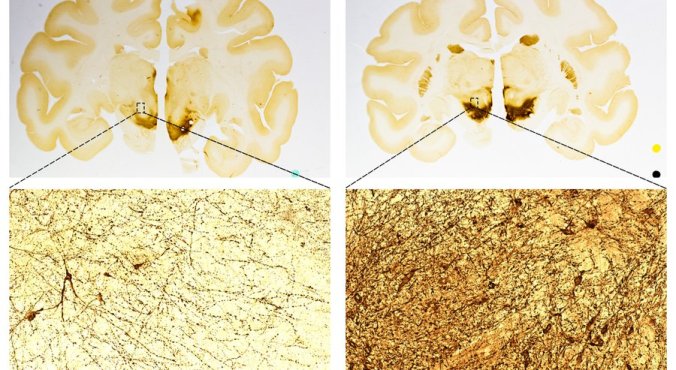

A comparison of primate brains to show an increase in the number of neurons after treatment with ISCO’s stem cells. The left side is a control sample. The right side is from a treated brain. — International Stem Cell Corp.